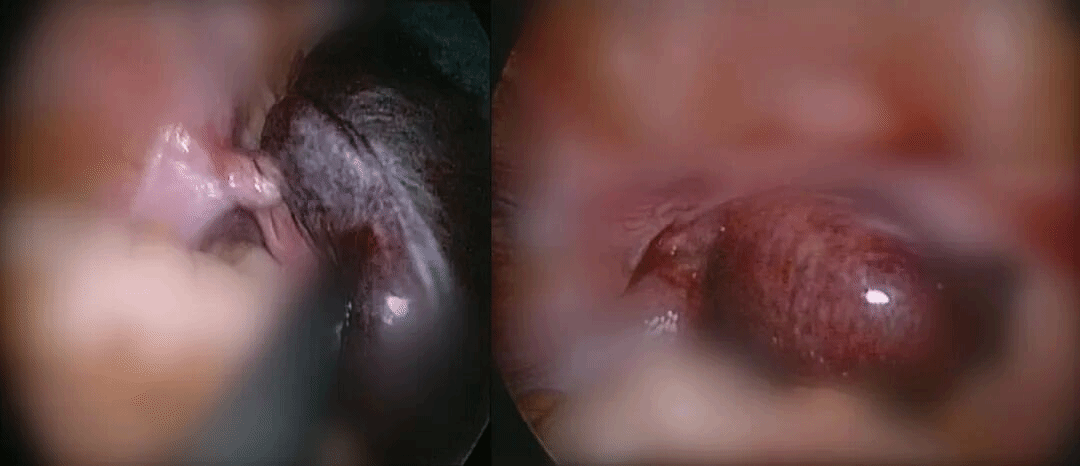

术中发现

卵巢扭转了1440°

卵巢因缺血而发黑、濒临坏死

团队在麻醉科协助下,成功复位卵巢。术后女孩的腹痛立刻缓解,更重要的是,为她保住了对未来生育和内分泌功能至关重要的器官。

卵巢复位前后